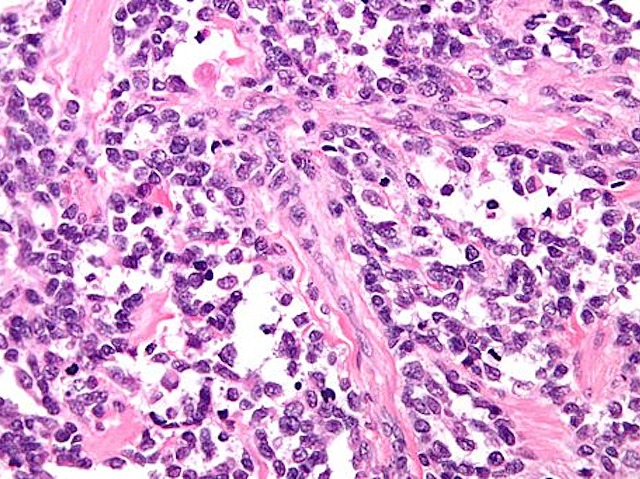

Identifying signature genetic mutations in various cancers has led to treatments that specifically target the flaw. But with rare cancers there may be too few patient samples available from which to discern any common fault. Travelling back in time, researchers have now shown that it’s possible to boost sample sets using tissue taken from patients as long as a century ago, and to be found stored in hospitals worldwide. Archived samples have been preserved using the standard paraffin wax procedure still in use today, and from which pathologists cut and stain sections to identify the disease – like this rhabdomyosarcoma [a rare muscle tumour] pictured. However, until recently gene analysis has only worked on freshly frozen tissue, often stored especially for the purpose. Now the technology has advanced, the readily available wax-embedded tissue can also yield the genetic code, and with it may follow targeted therapy for rare tumours.